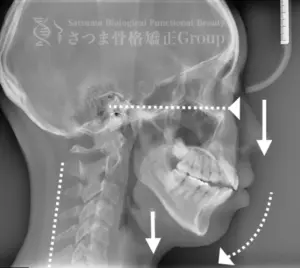

• 顎位のズレ

• 咬合の乱れ

• 頭位・頸椎姿勢のバランス

• 筋肉・関節の負担部位

を精密に分析し、

患者様ごとに最適な施術プランを立て、歯科治療+骨格施術をしていきます。